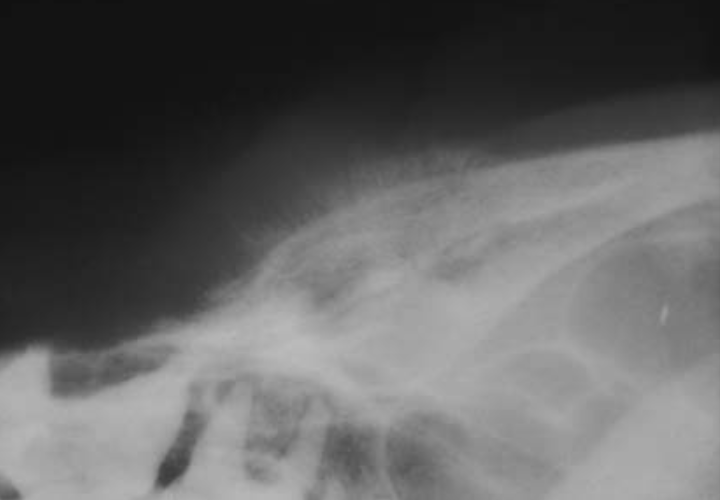

A

Osteosarcoma of the frontal bone with a sunburst periosteal reaction.